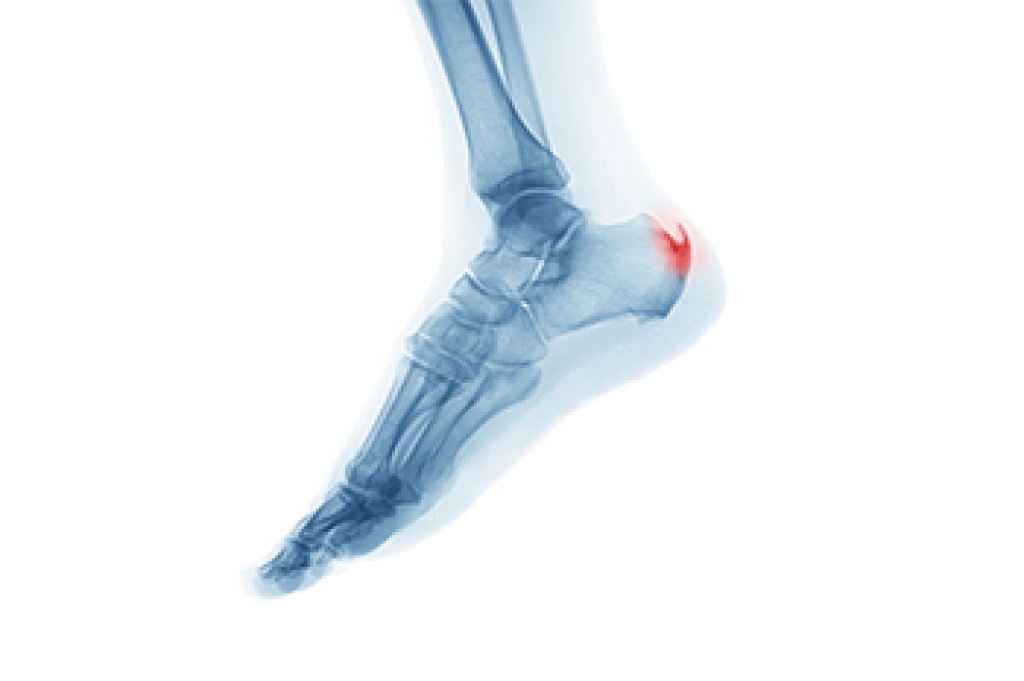

A heel spur is a bony growth that develops on the underside of the heel, often associated with inflammation of the foot muscles and ligaments. It commonly forms over time due to repetitive stress and strain on the plantar fascia, the strong band of tissue running from the heels to the toes. Symptoms include heel pain that may feel sharp or aching and is often worse after periods of rest or when first standing. Risk factors include high impact activities, sudden increases in exercise intensity, wearing improper footwear, and prolonged standing. Without proper care, discomfort may persist and affect mobility. A podiatrist can help by diagnosing the condition, reducing inflammation, and recommending supportive treatments. If you have heel pain and it has become difficult to complete daily activities, it is suggested that you consult a podiatrist who can guide you toward effective relief solutions.

Heel spurs are formed by calcium deposits on the back of the foot where the heel is. This can also be caused by small fragments of bone breaking off one section of the foot, attaching onto the back of the foot. Heel spurs can also be bone growth on the back of the foot and may grow in the direction of the arch of the foot.

Older individuals usually suffer from heel spurs and pain sometimes intensifies with age. One of the main condition's spurs are related to is plantar fasciitis.